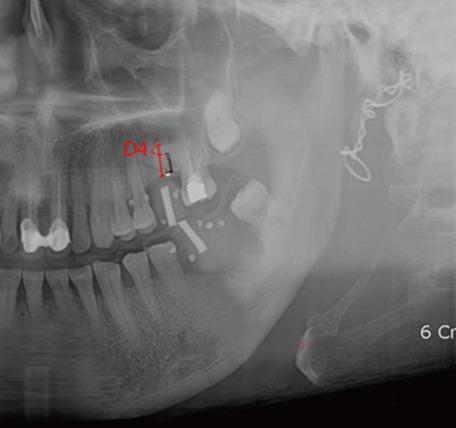

Ten fresh cadavers without posterior teeth were used, and twelve practitioners who had no experience of implant surgery performed implant surgery after 10 hours of basic instruction using conventional surgical guide based on CBCT or DPR. Two types of measurement error were evaluated: 1) the presurgical measurement error, defined as that between the presurgical and postsurgical measurements in each modality of radiographic analysis, and 2) the measurement error between postsurgical radiography and the real specimen.

The mean presurgical measurement error was significantly smaller for CBCT than for DPR in the maxillary region, whereas it did not differ significantly between the two imaging modalities in the mandibular region. The mean measurement error between radiography and real specimens was significantly smaller for CBCT than for DPR in the maxillary region, but did not differ significantly in the mandibular region.

Presurgical planning can be performed safely using DPR in the mandible; however, presurgical planning using CBCT is recommended in the maxilla when a structure in a buccolingual location needs to be evaluated because this imaging modality supplies buccolingual information that cannot be obtained from DPR.